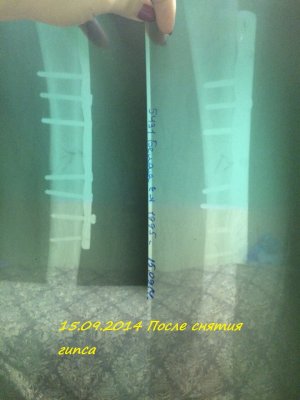

Здравствуйте! Мне 19 лет. 16.07.2014 года у меня случился закрытый перелом с/3 правого бедра со смещением. Произошло это так: я решила заниматься бегом. Каждый день бегала по стадиону минут 30-40. Получилось так, что я бежала, потом споткнувшись правой ногой, вернее как только я споткнулась, услышала хруст и упала на левую сторону. Сначала вообще не поняла, что произошло. Попыталась пошевелить ступней, особых болевых ощущений не испытала и решила попробовать встать, как только я попыталась поднять ногу, я увидела как у меня в бедре "шевелятся" кости. В итоге вызвали скорую, сделали рентген (все снимки я загрузила), поставили спицу под б/берцовую кость, почти под коленом, и я лежала 6 дней на вытяжке. 22.07.2014 года был проведен Экстрамедуллярный остеосинтез правого бедра пластиной АО (все пишу из выписки медицинской карты)Причем, прошу заметить на снимках может быть не видно, во время операции обломалось сверло, и пластину не закрепили по краям, я, конечно, мало что понимаю. 4.08.2014 года мне наложили гипс и отправили домой. 15.09.2014 года сняли гипс, я стала постепенно разрабатывать ногу, ходить, примерно 1.10.2014 года я стала ходить с тростью, все вроде бы шло на поправку. 23.10.2014 года меня выписали, и я уехала учиться в ВУЗ. Примерно вначале декабря я упала с лестницы(примерно со 2-ой ступеньки, при этом все это время я ходила с тростью). Стала болеть нога, я пошла в больницу, вновь снимок. Сказали все нормально-срастается. Назначили магнит(10 дней), отходила я на магнит. Все стало нормально, после НГ я могла ходить без трости, немного хромала, носила ее с собой, и когда уставала-ходила с ней. Вначале марта, примерно с 5-ого числа, стали мучить очень сильные боли, причем болело колено, очень тянуло берцовые кости, иногда беспокоило место перелома, вновь иду в больницу, опять снимок. И УЖАС! На снимке видно, как у меня кривится кость, чуть ли не ломаясь пополам, и переломана пластина. Мне говорят, что нужно делать операцию, врач сказал, что пластину не будут ставить повторно, эту уберут, все почистят и поставят штифт.